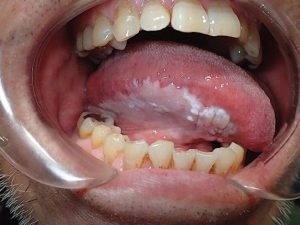

Bạch sản niêm mạc miệng: Triệu chứng và nguyên nhân gây bệnh

Bạch sản niêm mạc miệng là một tình trạng trong đó có sự xuất hiện...